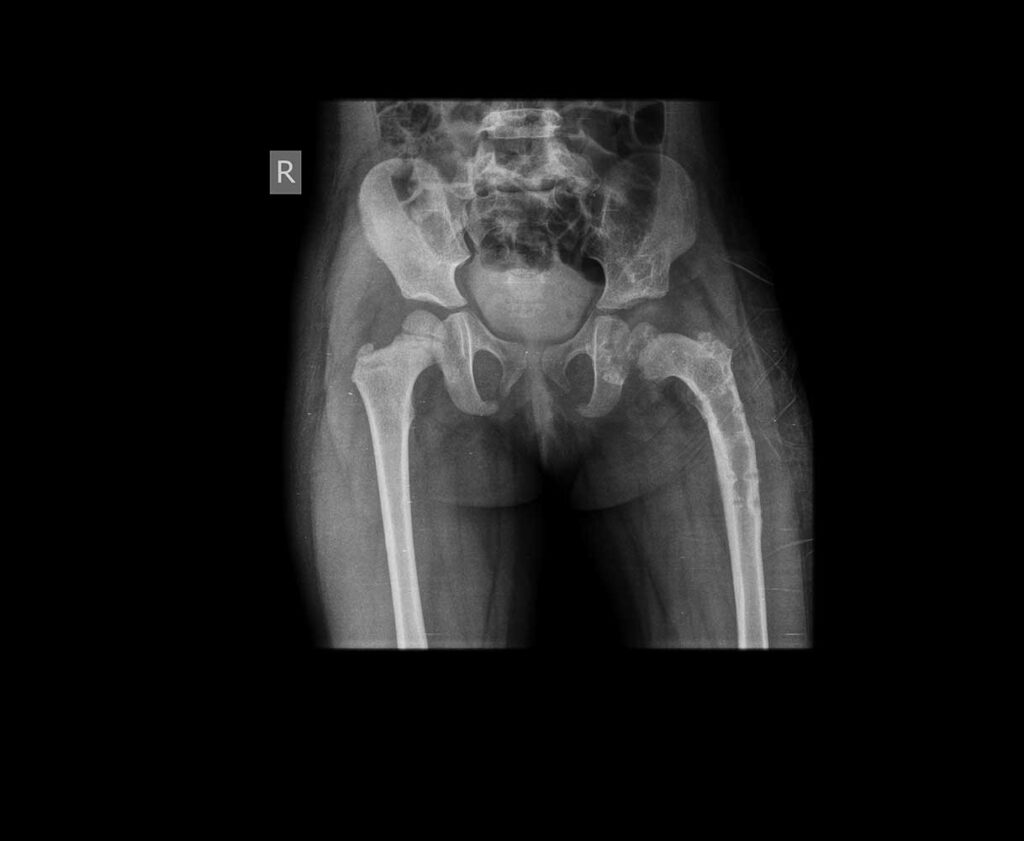

Two years After surgery

Osteotomy: If the dislocated hip joint is not corrected at young age, the bones making up the hip joint (upper end of thigh bone and the hip socket) would gradually deform so that even if we just put the ball back into the socket it may not stay there firmly- it will slip out again! To prevent this children older than 1½ years of age, in addition to open reduction the surgeon may cut the deformed bones and re-shape them- this is called osteotomy. DDH is a disease for which early detection and treatment is crucial. As the child becomes older, the grade of treatment becomes higher (more major surgeries are needed) and the results of treatment are less satisfactory even after proper treatment.